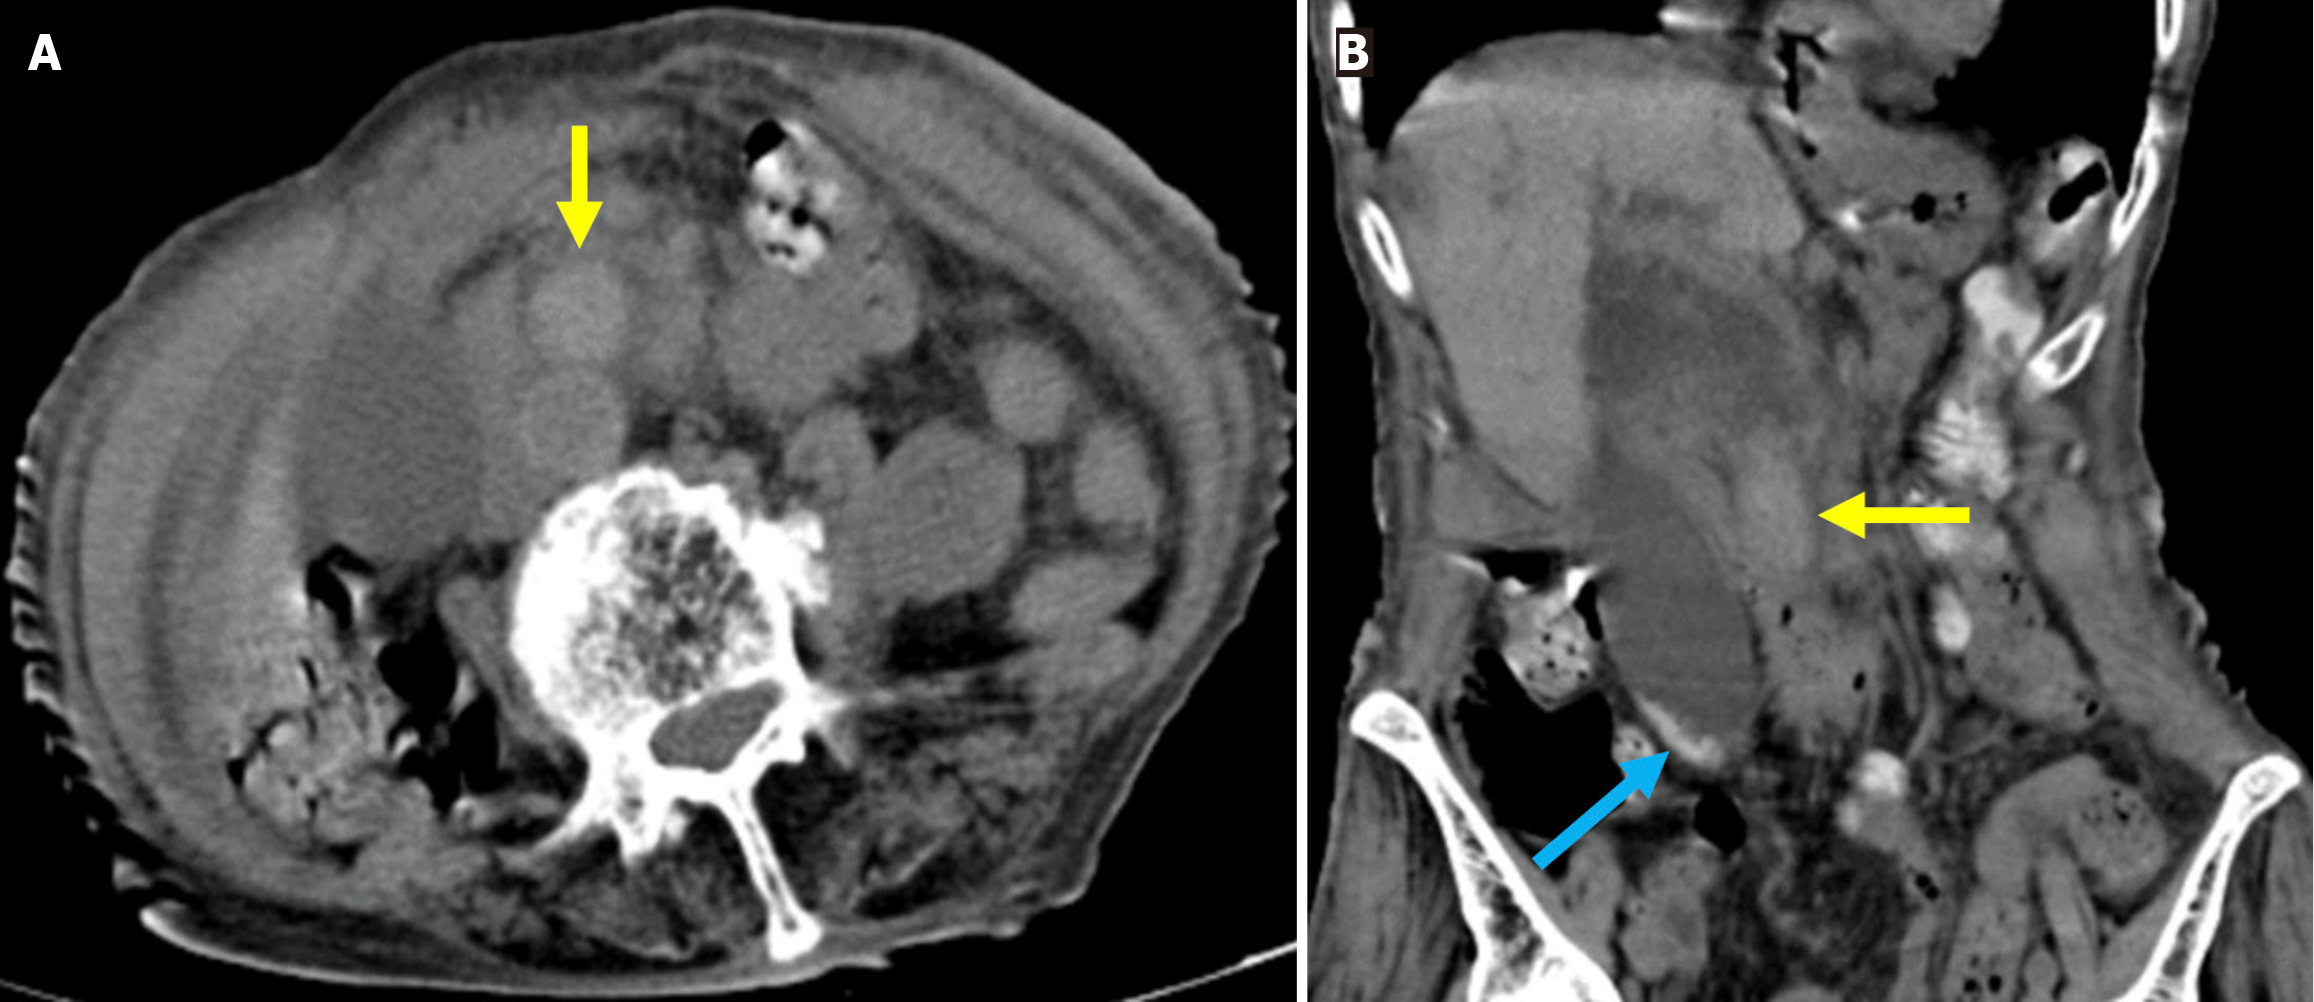

Stent migration: Proximal or distal migration of biliary stents occurs in 5%-10% of patients after stent placement. Gastrointestinal penetration or transmural perforation related to stent migration is uncommon in clinical practice (Figures 16 and 17)[80,81]. Proximal migration refers to the displacement of the stent into the right or left main bile duct, whereas distal migration indicates movement beyond the papilla[78]. Migration rates are lower in malignant strictures, particularly when using multiple stents. In benign strictures, long stents, proximal strictures, and post-cholecystectomy strictures have been associated with distal migration. Conversely, short stents, distal strictures, and the absence of post-cholecystectomy changes are more commonly linked to proximal migration[80,82].

Figure 16  Proximal stent migration. A and B: Axial (A) and sagittal (B) contrast-enhanced computed tomography of a 73-year-old male patient with a history of biliary stenting. He presented with persistent abdominal pain following revision of the common bile duct stent 1 week prior. The patient developed progressive jaundice, pruritus, and recurrent fever. Laboratory tests revealed elevated levels of bilirubin, aspartate aminotransferase, and alanine aminotransferase. The stent, which should be located within the common bile duct, migrated proximally into an intrahepatic bile duct and extended toward the subcapsular region of hepatic segment IV (yellow arrows).

Figure 17  Distal stent migration. A: A 56-year-old male patient with a history of endoscopic retrograde cholangiopancreatography (ERCP) and biliary stenting presented with right lower quadrant pain lasting for 3 days. The coronal noncontrast computed tomography (CT) images demonstrated distal migration of the stent into the cecum (orange arrow); B: An 85-year-old patient with a history of ERCP and biliary stenting presented with jaundice. The previous stent was not visualized during ERCP for stent revision, and re-stenting was performed (yellow arrow). Post-procedural coronal contrast-enhanced CT revealed distal migration of the previous stent into the ascending colon (blue arrow).

Distal migration of a biliary stent typically involves passage through the gastrointestinal tract without complication. However, there is the potential for perforation of the duodenum, jejunum, ileum, cecum, or colon[83]. Biliary stents cause perforation more frequently than pancreatic stents when migrating distally and may be related to the steeper exit angle of biliary stents into the duodenum[84]. These types of perforations are not included in the Stapfer classification nor other ERCP-related perforation systems. They present with pneumoperitoneum or retroperitoneal gas accumulation, fluid collections, or direct evidence of duodenal wall disruption on abdominal CT. While there are no specific guidelines for the management of stent-related perforations, imaging findings and the patient’s clinical status are critical for determining the appropriate intervention (i.e. surgical or endoscopic) (Figure 18)[79].

Figure 18  Distal stent migration and duodenal perforation. A and B: Coronal (A) and sagittal (B) contrast-enhanced computed tomography images in a 77-year-old female patient with a history of endoscopic retrograde cholangiopancreatography and biliary stenting for cholangitis, who presented with severe abdominal pain. Tachypnea and agitation were observed and were accompanied by nausea, fatigue, and impaired oral intake. Laboratory tests revealed elevated leukocyte counts, C-reactive protein levels, and lactate levels. The stent was found to have migrated distally into the duodenum and perforated the distal portion of the second part of the duodenum (yellow arrow). High attenuation-free fluid, suggestive of hemorrhage, was observed in the perihepatic region and mesentery (blue arrows). The liver exhibited heterogeneous contrast enhancement, consistent with impaired perfusion that was likely related to ischemia (orange circle). Emergent surgical intervention was required.